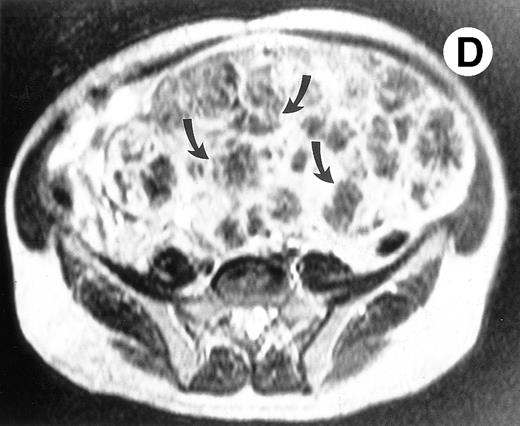

Surgical pathology showed a 6.5-kg spleen with nodular appearing external surfaces and focal subcapsular infarcts, ranging in size from 0.5 to 3.4 cm. Serial sections showed rubbery and focally fibrotic surfaces (Fig 2A). This correlated with his presurgical axial T2-weighted MRI, which demonstrated multiple low signal intensity nodules not seen on T1-weighted views (Fig 2B through D). Although MRI is useful in monitoring response to therapy, this case demonstrates that volumetric measurements alone may not be adequate, especially when there are multiple areas of decreased signal intensity on T2-weighted STIR images. Both splenic nodules and infarcts are common in Gaucher patients, occuring in approximately 30% and 32% of patients, respectively.5 Thus, the volume free of nodules and infarct may be a more reliable measure of response to enzyme therapy in these patients.

(A) Photograph of the patient's spleen showing multiple nodules (arrows) with area of subcapsular infarcts (curved arrows). (B) Coronal STIR MR image of the (L) liver and spleen (IR 2450/100/30) shows multiple low signal intensities nodules (curved arrows) in the enlarged spleen. (C) Axial T1-weighted (SE 300/10) MR image shows splenomegaly with no focal splenic signal abnormality. (D) Axial T2-weighted (SE 4293/80) MR image of the spleen at the same level as (C) shows multiple low signal intensity nodules in the enlarged spleen (arrows).

Enzyme replacement therapy can effectively improve the multisystem involvement seen among patients with Gaucher disease. Because medical therapy is now available, the appropriate criteria for splenectomy must be reconsidered. Although the medical consequences of delaying splenectomy in this case may have been minimal, the economic burden (>$800,000 for this patient) cannot be easily overlooked. A suboptimal hematologic response to an adequate trial of enzyme replacement is an appropriate indication for splenectomy. The prohibitive cost of enzyme may be sufficient criteria in certain circumstances. A T2-weighted MRI showing an enlarged spleen with multiple hypodense nodules may indicate that large damaged regions are inaccessible to infused enzyme, necessitating splenectomy. Other emergencies, including the need for rapid surgical correction of thrombocytopenia, an inferior vena cava syndrome, severe abdominal pain crises, and splenic abscesses, continue to be valid rationale. The question of whether, in similar patients with massive organomegaly, splenic nodules, and thrombocytopenia, splenectomy should be the initial therapy, remains to be determined.